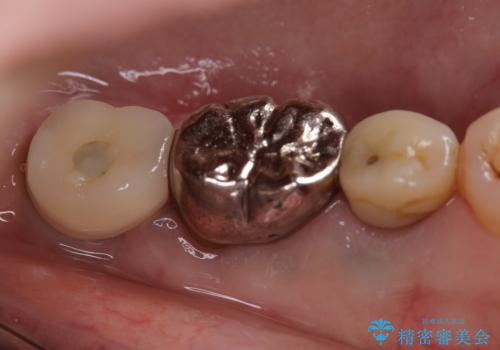

![[ インプラント体・カスタムアバットメント・ジルコニアクラウン ] インプラントの構造の症例 治療前](https://seimitsushinbi.jp/wp/wp-content/uploads/2024/02/d7b3d7509c0cc77833268d7096e1730b-500x350.jpg?v=1708928260)